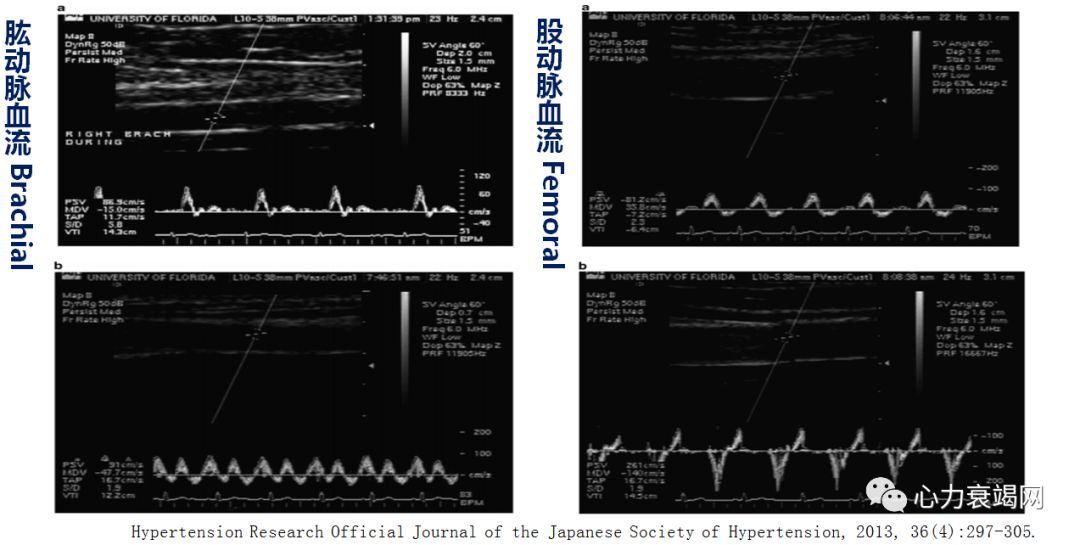

体外反搏的即时血流动力学效应

Acute Hemodynamic Effects of EECP

Increase Coronary Artery Blood Flow

体外反搏治疗与患者冠脉循环反应

EECP血流动力学效应

——改善外周阻力血管血流